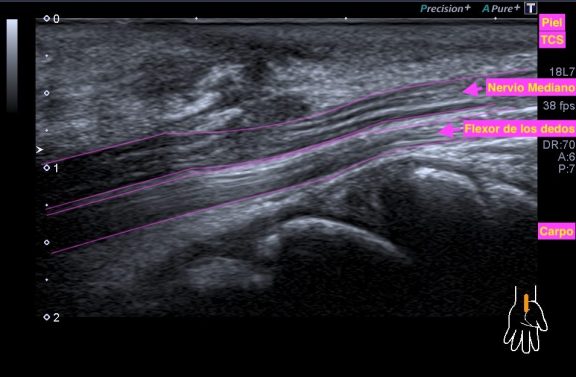

Un breve recuerdo anatómico de la zona tanto en eje largo como en eje corto (longitudinal o transverso), fig 3 y 2 respectivamente, . Fíjese la/el lectora en el posicionamiento del pictograma de referencia.

Repasamos anatomía y aprender una forma de estudio de la inserción del tendón del recto anterior del cuadricipital donde vas a ver esas fibras, perfectas. Como se tiene que ver para buscar entensopatías a ese nivel y para que las reconozcas en otras localizaciones típicas, aquiles, epicóndilo…etc…

Lo primero que hice fue tumbar al paciente en la camilla, con una sonda de alta frecuencia posicionada en la zona de dolor, explorando dicha zona en eje largo respecto del fémur, es decir, corte longitudinal.